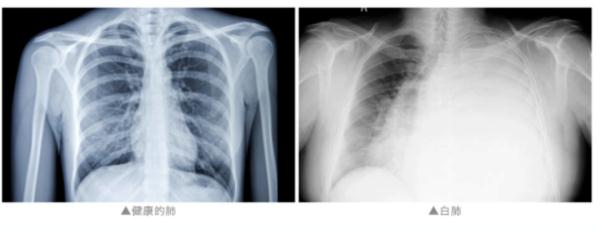

近日,“女子硬扛流感10天白肺”的话题登上热搜。此前报道:流感≠感冒!女子硬扛流感10天险丧命!有这些症状拖不得

王越表示,出现这种情况的患者大都存在一定的基础疾病,比如,一些肺部的疾病,慢阻肺、哮喘等等,或者有一些心脏,包括血管的问题。有的患者还有一些肿瘤,或者正吃着一些影响免疫功能的药物等等,这些人都是高危人群。还有一部分人可能确实发展成肺炎了,类似“病毒开路,细菌捣鬼”,可能混合了其他的问题。

@所有人:当前呼吸道传染病高发!这类人群更易“中招”!

白肺相关情况/源自网络

因此,呼吸道疾病的患者需要观察自己的症状,如果出现持续高热不退、气短、基础病加重等情形,应该及时到医院就诊。王越提示,像持续的高热不退,出现了非常明显的气短或者说喘憋,这些可能往往意味着肺炎,或者是出现了更加严重的呼吸系统的问题。像高危人群,包括有基础病的人群,其实建议如果有症状要尽快就诊。因为他本体的免疫功能可能没有那么好,所以可能反应起来就没有这么剧烈。这也是很重要的,可能会延误诊断和治疗的一个节点。